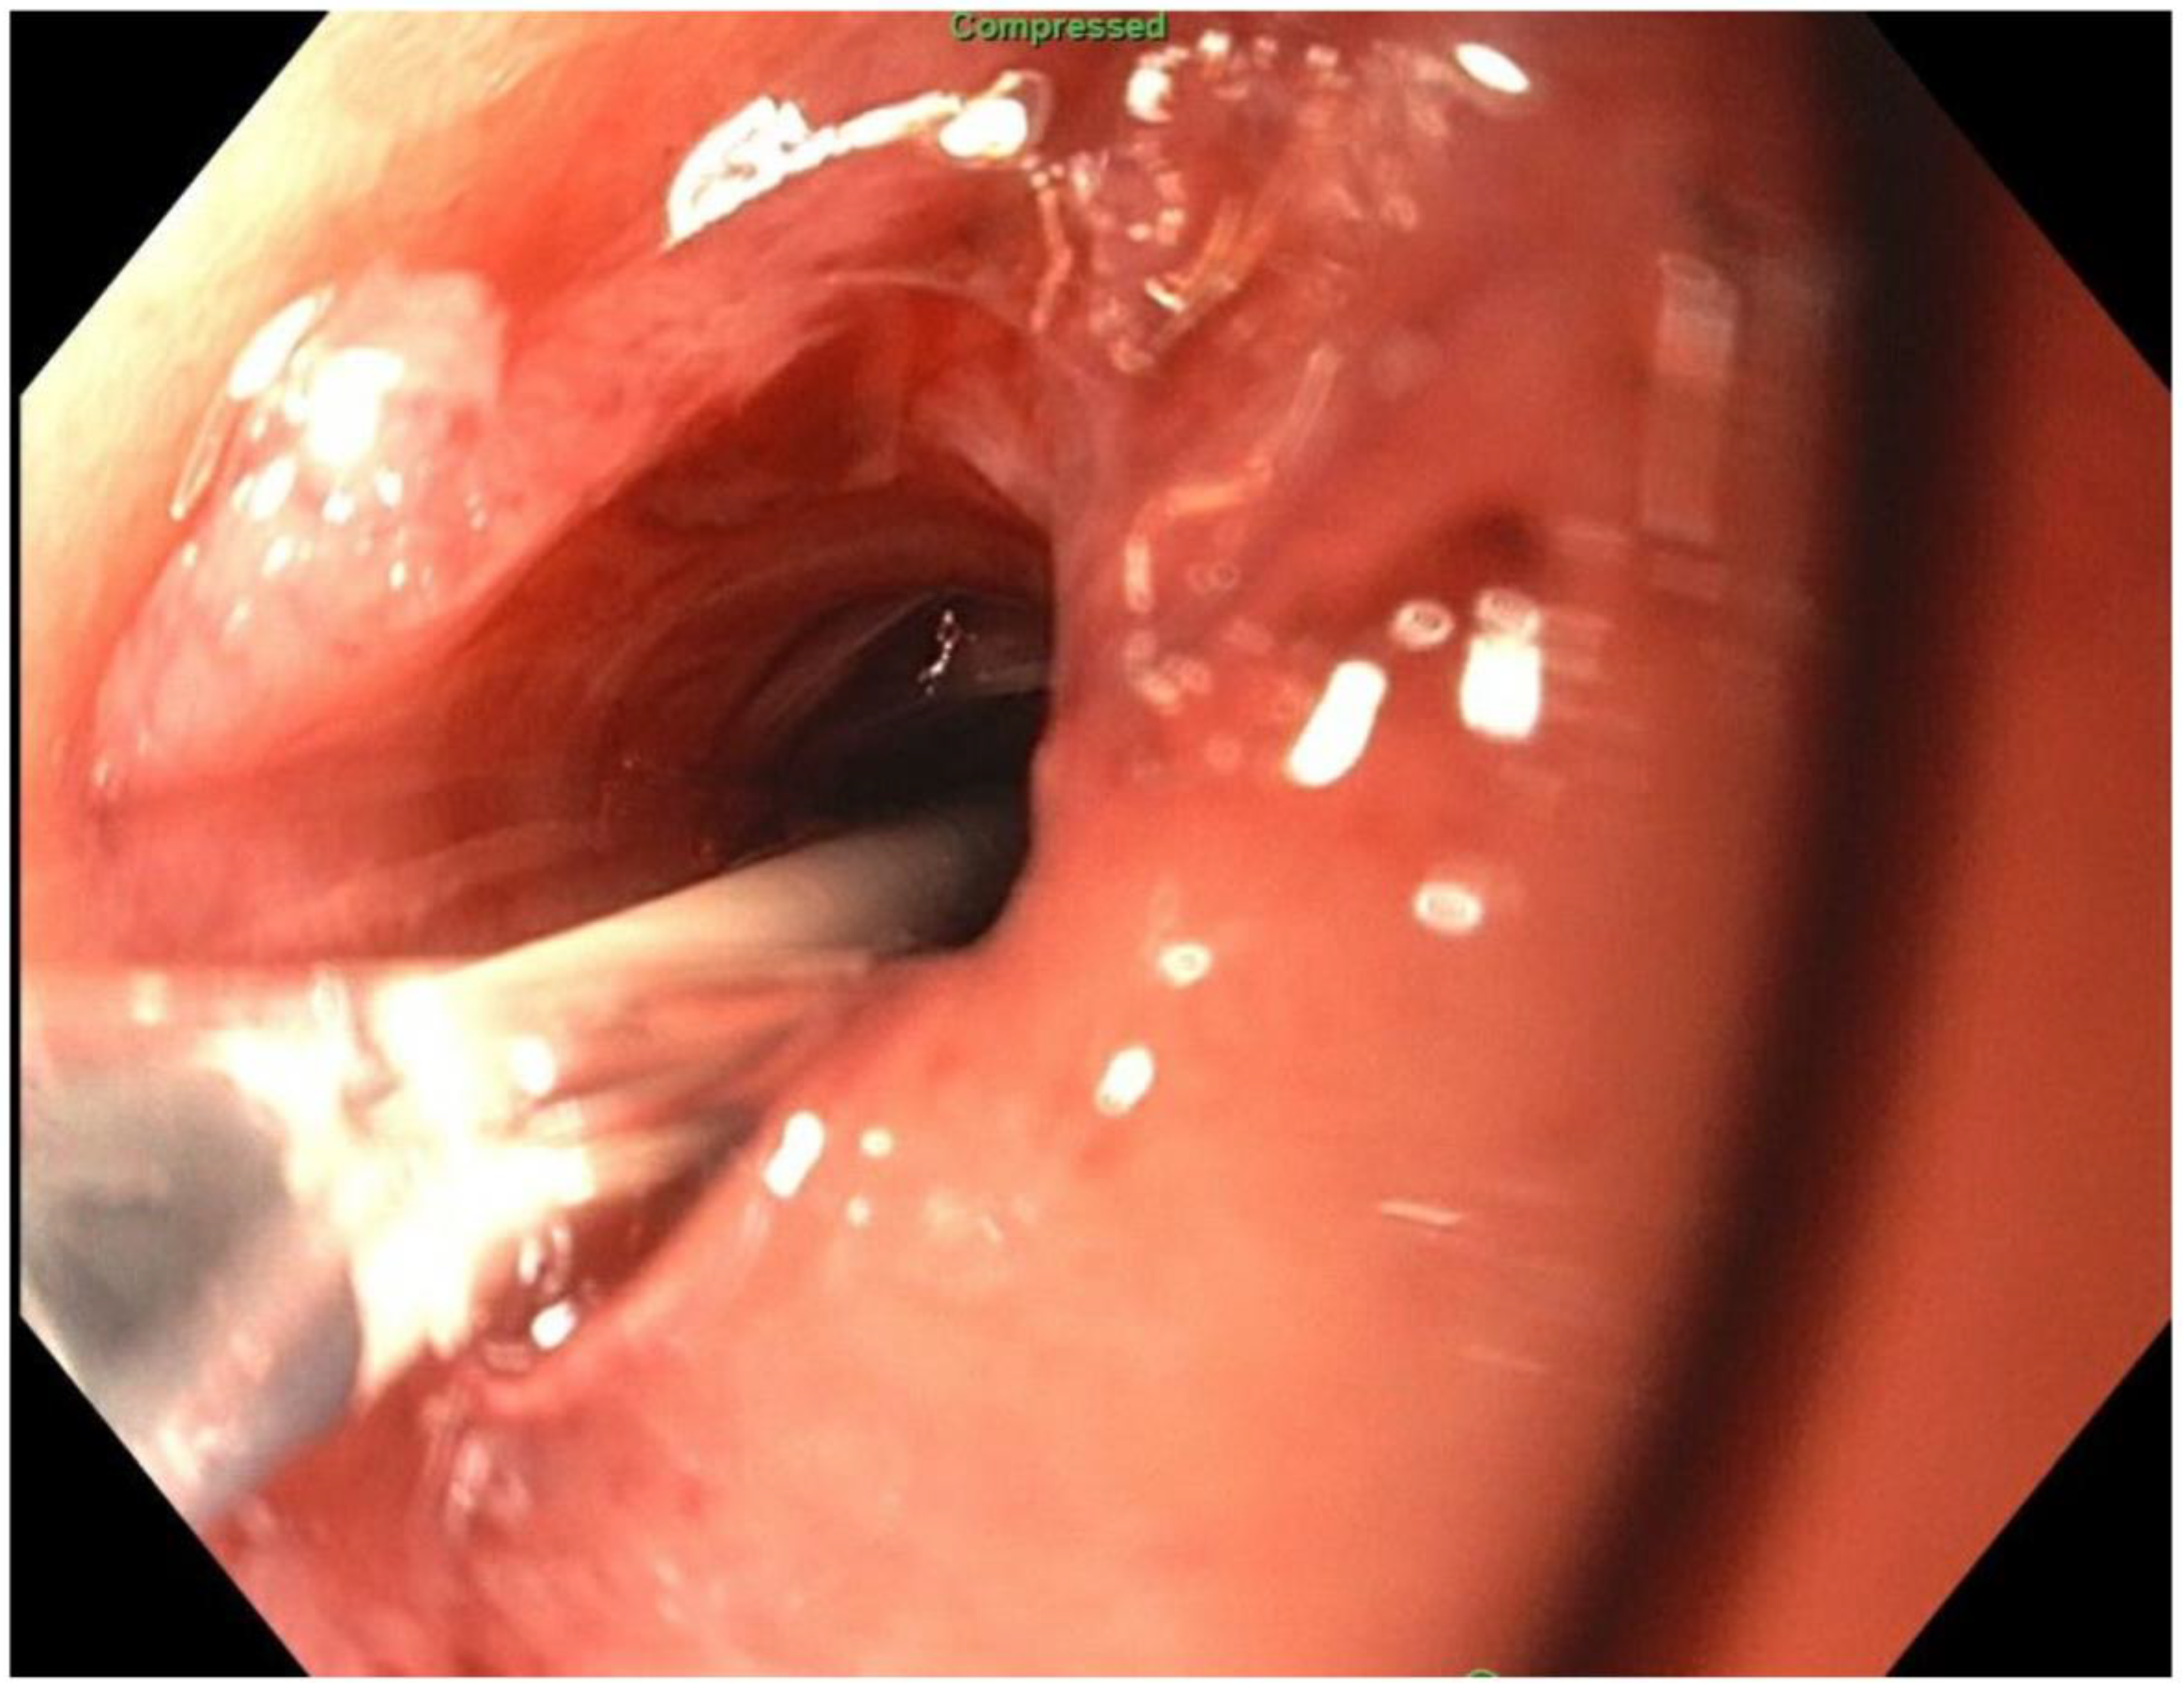

2. Detailed Case Description